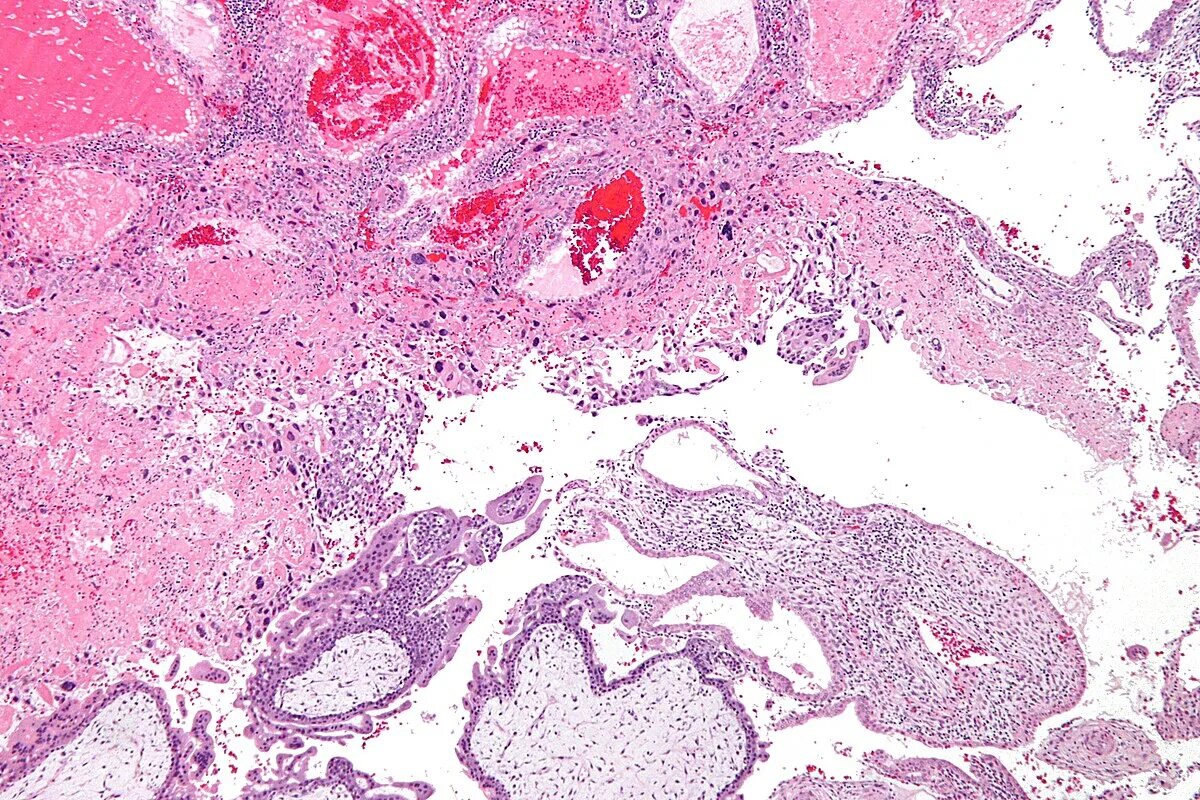

Эндометрит гистология